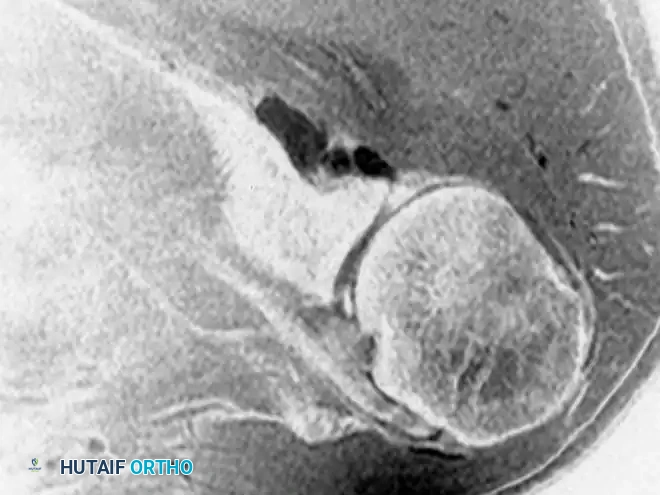

Spinoglenoid Notch Ganglions and Suprascapular Nerve Entrapment

Paralabral cysts, often presenting as soft-tissue ganglions, are frequently associated with superior labral anterior-posterior (SLAP) tears or posterior labral tears. When these cysts extend into the spinoglenoid notch, they can compress the suprascapular nerve.

Biomechanics and Pathophysiology:

The suprascapular nerve provides motor innervation to the supraspinatus and infraspinatus muscles. Entrapment at the spinoglenoid notch selectively denervates the infraspinatus, leading to isolated external rotation weakness and visible muscle atrophy. The one-way valve mechanism of a labral tear allows synovial fluid to pump into the cyst, exacerbating the compression.